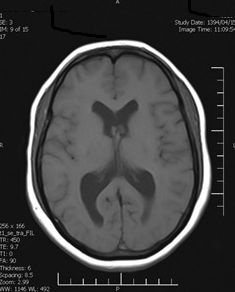

Background: Cavernous hemangiomas are common benign vascular malformations. Their existence in the intraventricular region is very rare. Case Reports: A 43-year old woman with an occipital headache was admitted to the emergency ward. Brain computed tomography scan showed mild hydrocephalus and multiple intraventricular isodense lesions. Imaging findings, especially of Gradient Resonance Echo imaging, were in favor of multiple intraventricular cavernous malformations. Conclusion: This is a rare presentation of multiple cavernous malformation as occipital headache without needing surgical intervention in this phase. Coexistence of periventricular plaques like Radiologically isolated syndrome of Multiple sclerosis is another unique aspect in this report. [GMJ.2017;6(1):61-65]